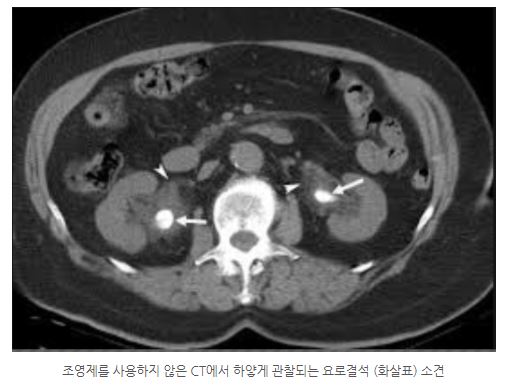

담낭/담도결석, 요로결석과 같은 석회화 병변은 밀도가 높아 CT에서는 하얗게 보이는데 뼈를 제외한 대부분의 생체조직의 밀도와는 다르기에 조영제를 쓰지 않고도 CT에서 잘 관찰됩니다. 이런 병변들은 MRI에서 까맣게 보여 주변과 잘 구별되지 않습니다. 비슷한 이유로 골절 진단에도 CT가 더 우수합니다. 이와는 반대인 공기의 경우 CT에서는 까맣게 보이는데 MRI에서는 영상의 왜곡을 유발합니다. 그래서 예를 들어 장천공처럼 복강에 없어야 할 공기를 찾아내는 데는 CT가 더 우수할 수 있습니다. 비슷한 상황으로 폐는 공기가 주성분이라 MRI의 역할이 적고, CT가 훨씬 우수합니다. CT의 해상도가 MRI보다 높다는 점도 중요한 이유입니다.